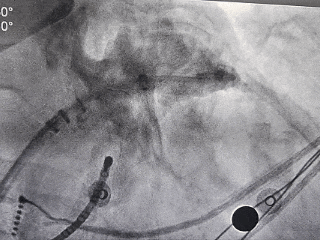

DSA造影复测缺损

右肩位:RAO 30° +CRAN 20°

肝位:RAO 30° +CAU 20°

术中肝位测量:

心耳开口直径:24.9mm

心耳深度:26.9mm